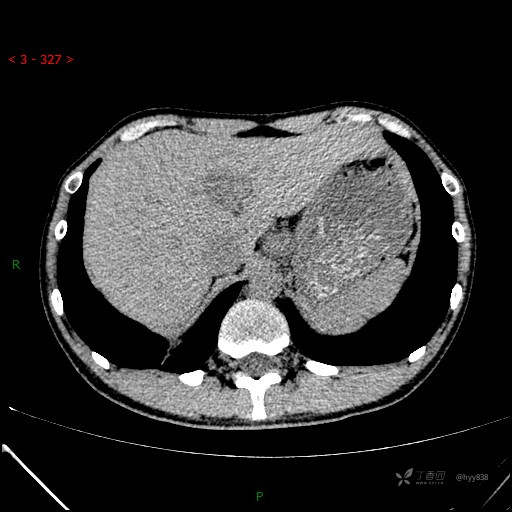

胸部CT平扫